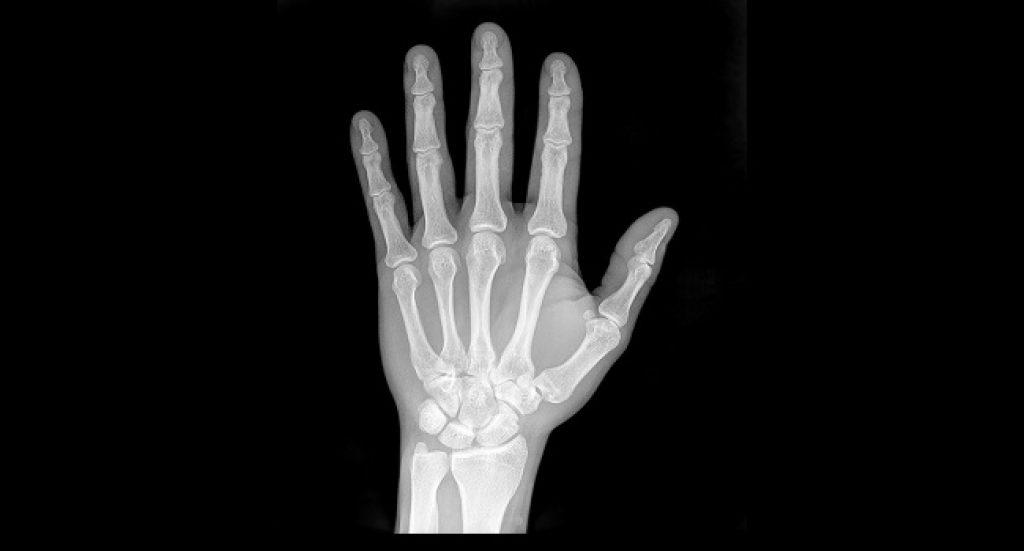

In the study, published in the journal Osteoporosis International, investigators from the University of Tasmania, Anhui Medical University and Nanjing Medical University estimated that in 2010 more than 2.3 million osteoporosis-related hip, clinical vertebral and wrist fractures occurred in the population aged 50 years and over.

The cost to the Chinese healthcare system was estimated to be approximately US$10 billion. Women accounted for 73 percent of the total costs, sustaining approximately three times more fractures than men.